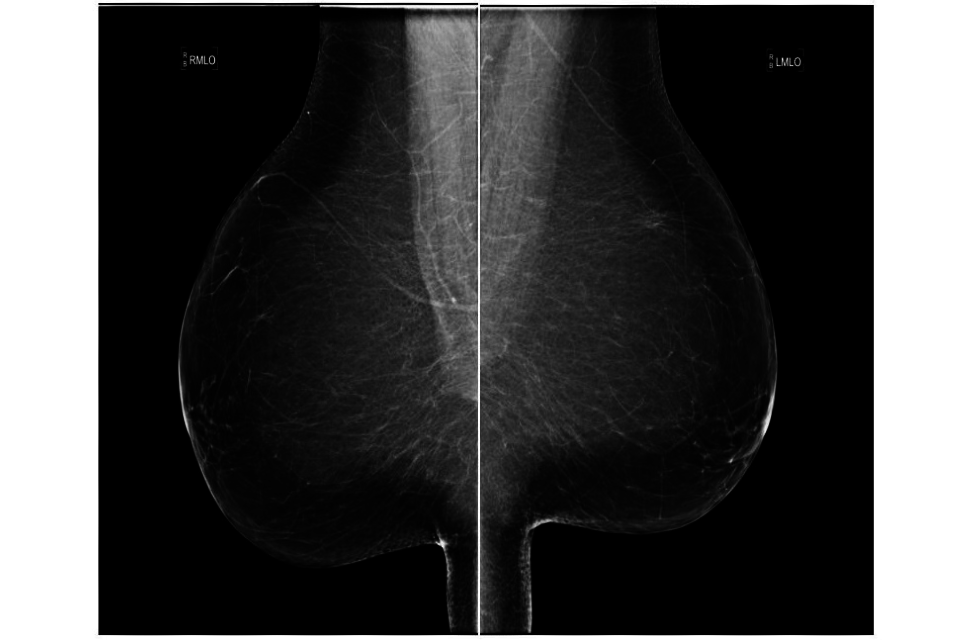

Specific criteria for MLO images

The specific criteria for assessing MLO images (see figure 1) are:

- correct patient ID and markers

- appropriate exposure

- adequate compression to hold breast firmly – no movement

- image sharp

- no artefacts obscuring image

- no obscuring skin folds

- nipple in profile (should normally be demonstrated in at least one view)

- pectoral muscle to nipple level or posterior nipple line (PNL)

- pectoral muscle at appropriate angle

- inframammary angle shown clearly

- symmetrical images

- whole breast imaged

An exmaple of an mediolateral oblique (MLO) image